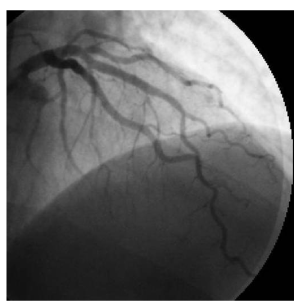

Figure 3: